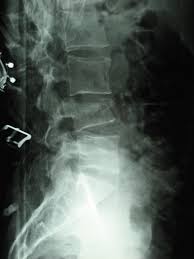

Le Tassement Vertebral Ou Fracture Vertebrale Une Urgence Chirurgicale

Le Tassement Vertebral Ou Fracture Vertebrale Une Urgence Chirurgicale from www.allodocteurs.fr